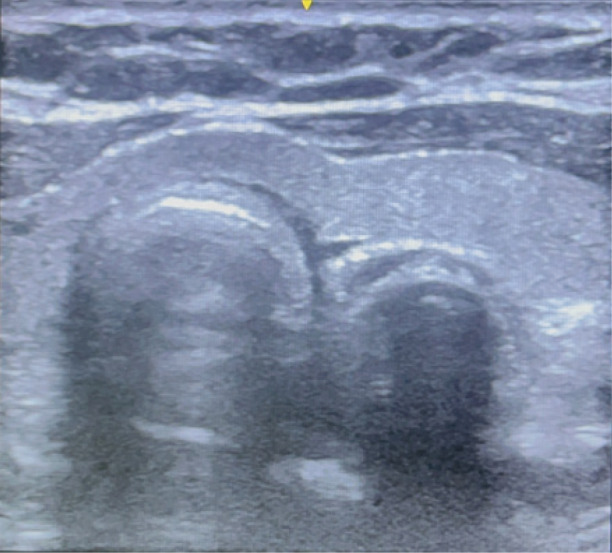

目的:气管插管成功是先进气道管理的关键步骤。气管插管成功的金标准是潮末二氧化碳(etCO2)监测,尽管最近的研究表明超声波也可以使用。在本研究中,我们通过比较超声和etCO2监测,探讨了气管插管成功的时间敏感性早期识别。方法:本研究纳入了104例在全麻下需要气管插管的择期手术患者。将取下面罩到超声显示气管颤振的时间与气管插管后连续6次超声波形的出现时间进行比较。结果:超声识别气管插管成功的时间为(21.63±7.38)秒,比超声检查(40.62±7.93)秒更快。结论:eCO2需要6次连续波形时间才能确认插管成功,且存在假阳性率。在不需要正压通气的低肺血流量患者中,如在心肺复苏期间,在创伤等高风险紧急插管中,或在可以实时确认插管的困难气道中,用超声补充金标准etCO2更快、更可靠。超声是一个可靠的和更快的工具,早期识别成功的气管插管比末潮二氧化碳。

Methods: The study included 104 patients who were posted for elective surgery under general anaesthesia requiring endotracheal intubation. The time from removal of the face mask to ultrasound visualization of flutter in the trachea was compared with that of the appearance of six consecutive capnography waveforms following endotracheal intubation.